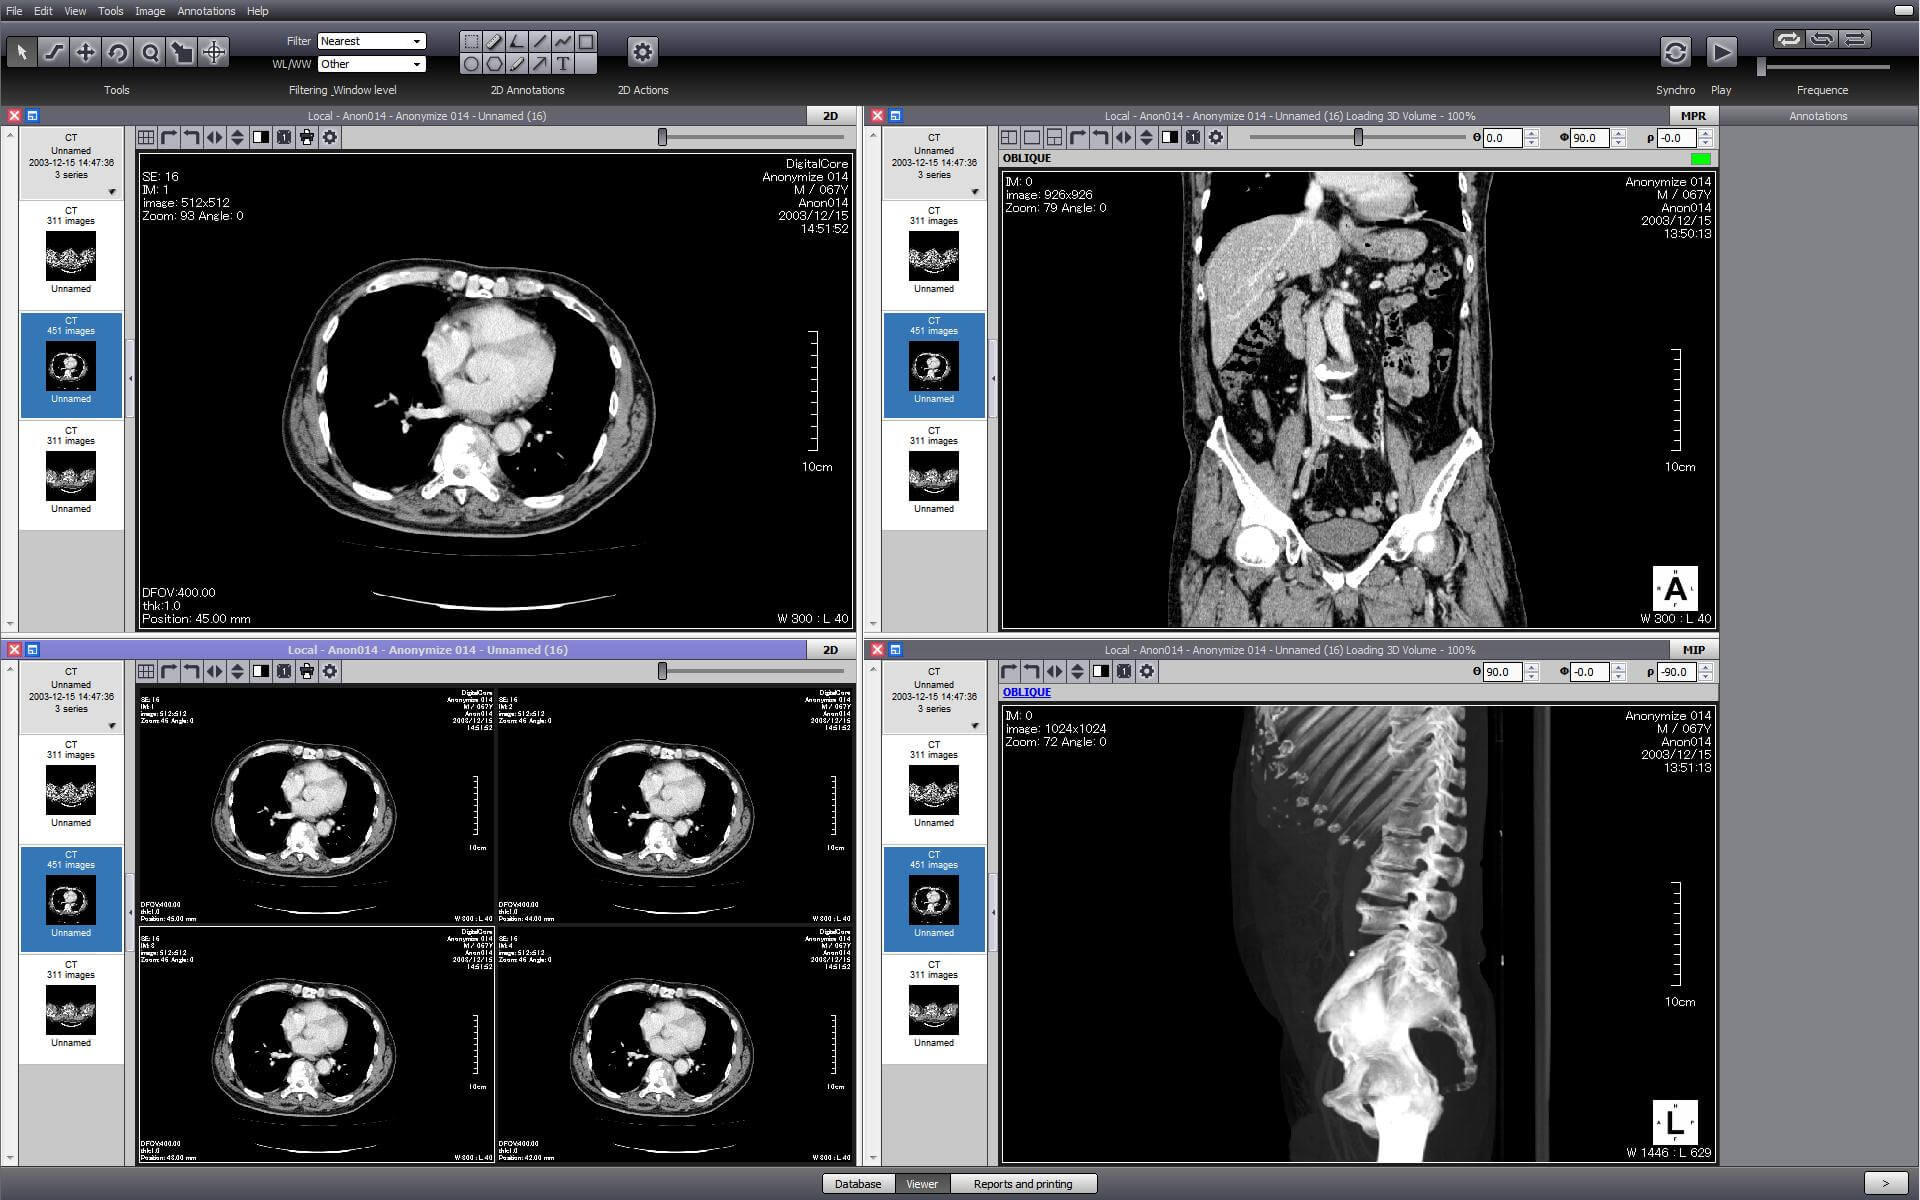

Horos is an open source DICOM viewer for Mac. It is actually the free version of an expensive DICOM viewer called Osirix MD, which is often considered to be the best DICOM viewer for Mac. It only runs on Mac OS, version 10.8 or higher. This software allows for most diagnostic techniques, including multiplanar reconstruction, maximum intensity projections, and volume rendering. It also has tools for manipulating images and making measurements.

One of the unique features of Horos is that it has a plug-in that allows uploading of images to Radiopedia, an online resource with a large number of reference cases and articles. Technical support is available through both phone and email. Horos, however, does not integrate to PACS free of cost. Cloud-based storage is available at an additional cost.

A free version of Osirix MD, called Osirix Lite, is also available to users. However, it does not allowing editing of imaging metadata, and image modifications come with a watermark. While this is good to get a feel for the parent software, it is not intended for regular medical use.